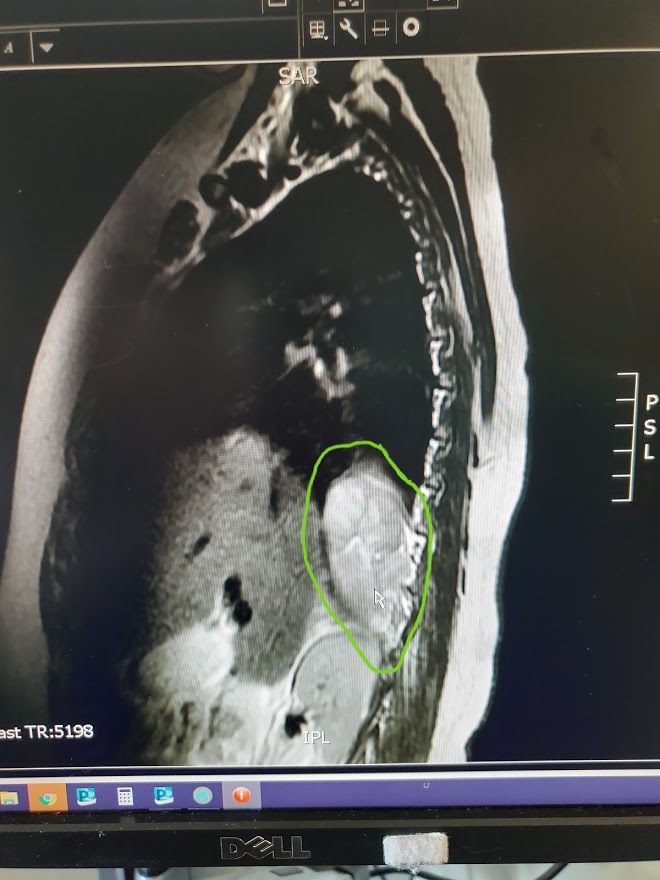

When they entered our room, they were gentle and kind. They were aware of the sensitivity of our aching hearts and they gathered around our sleeping baby girl with such tender kindness. After introductions they confronted the mass, showing us the images of the CT scan we had seen the night before where they had previously suspected an abscess on the Kidney. It was then, in that fragile moment that the doctor pointed to the screen and showed us where the mass was. It was huge. I cried as I studied the image and could see it’s foreign tissue invading her little body, pushing up against her spine, squeezing into un-invited areas. How it was missed, we do not know but what we do know is that there were a lot of little steps, steps we like to call miracles, that led us to where we were right in that moment. The mass was found and now we can move forward in finding out what he is and what he is doing there.

The mass measures 8 x 3.5 x 4cm. It’s ugly and it makes me want to scream. How long has it been growing? What could have caused it? If it is Cancer, why hasn’t she had any other symptoms? Is it hurting her? Where do we go from here?

They took our Savannah for an MRI to give us better imaging. It was that first gut wrenching feeling of having to let them take her and leave us behind. But Savannah was excited and ready for the adventure. She waved goodbye to us and sent us on our way. In the quiet short minutes that followed, Brannick and I found ourselves sitting in her hospital bed surrounded by silence. It was the first quiet moment we had together since the ER the night before. We sat there holding hands, processing the emotions that followed the discussion with the Oncology team. And then we prayed. We prayed with longing, with humility, with pleading hearts for our little girl to be ok. Together, in that hospital bed, we felt peace. Right now, it hurts. Right now, we ask why? We wonder. We wait. But we know, it’s gonna be ok. It’s gonna be ok. We will deal with whatever comes in the days ahead because it’s gonna be ok…. It’s gonna be ok!